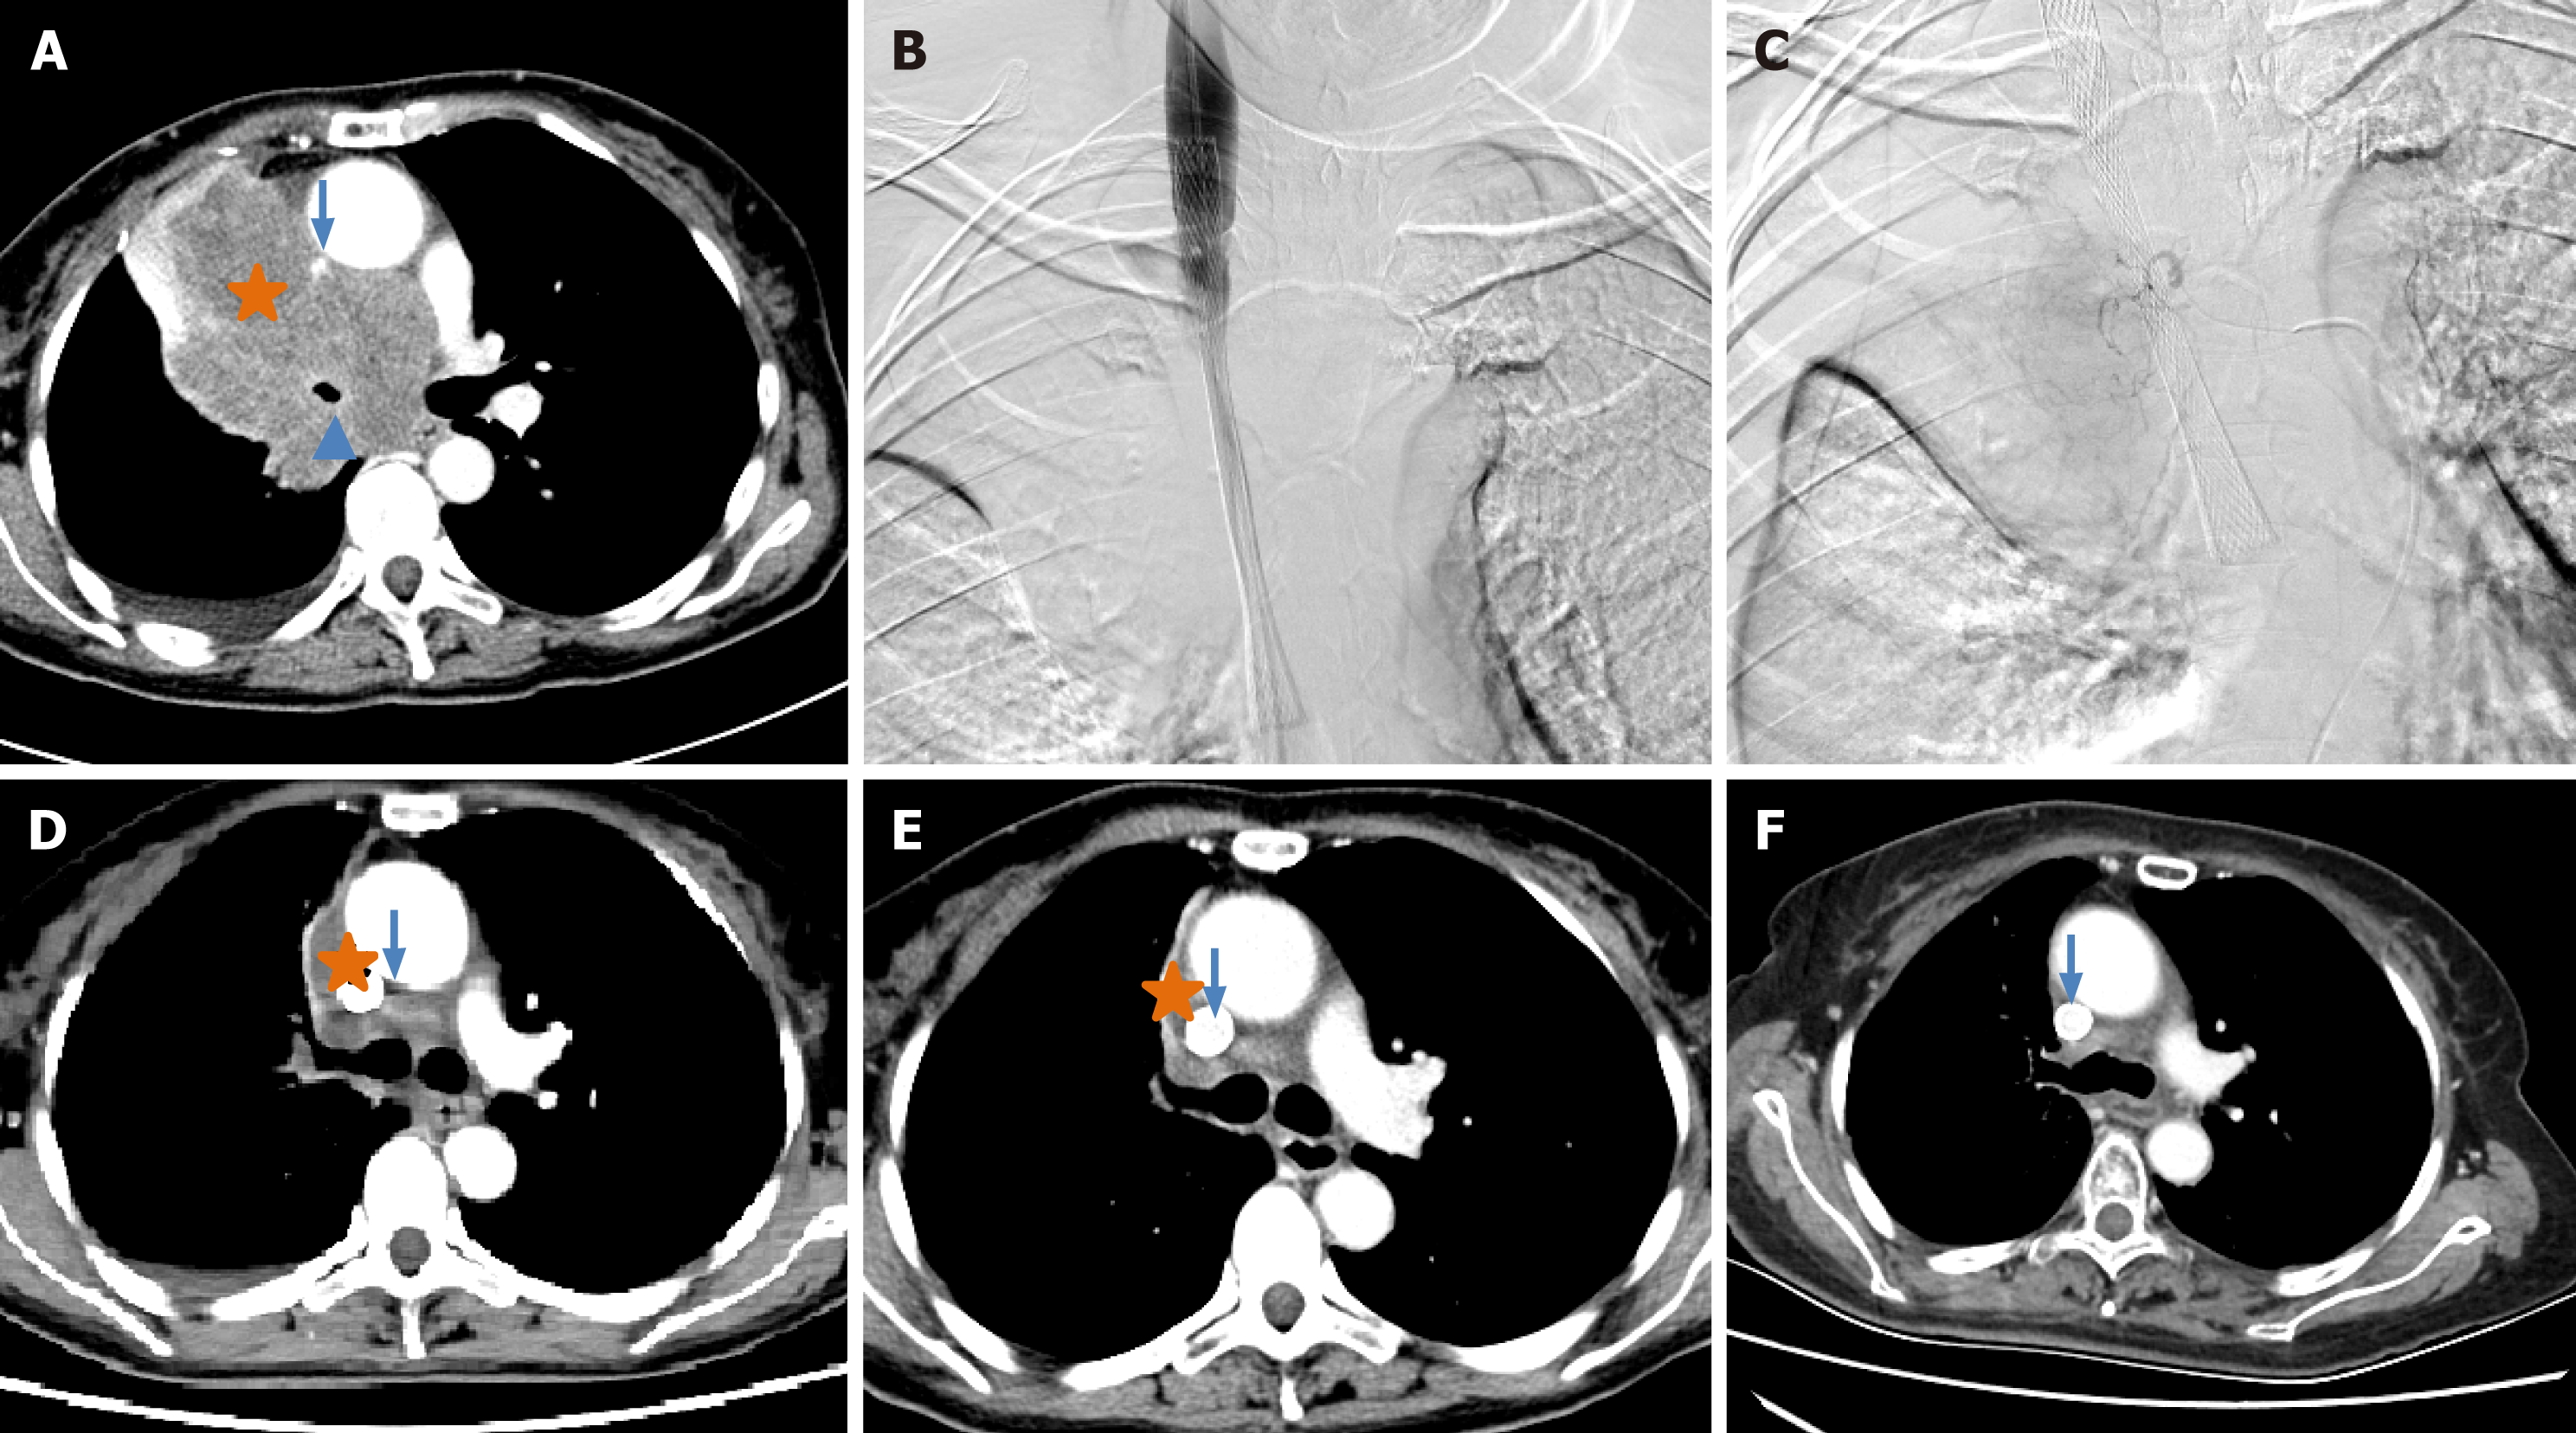

This retrospective study was approved by the Institutional Review Board of Zhengzhou university committee on human investigation, with all methods conducted in compliance with the relevant guidelines and regulations. As this study was designed as a retrospective study with clinical data analysed retrospectively and anonymously, the need for informed consent was waived by the Institutional Review Board of the First Affiliated Hospital of Zhengzhou University (No. 2023-KY-1002-002). All records were de-identified and stored in encrypted computer after data collection. A total of 123 patients with unresectable NSCLC who were treated in our department from July 2016 to July 2023 were retrospectively analysed. The inclusion criteria: (1) Biopsy proven NSCLC; (2) TNM stage II-IV according to the American Joint Committee on Cancer (AJCC) 7th Edition Cancer Staging System (Figures 1A, 2A, 2B, 3A and 3B); (3) Unresectable NSCLC or refused surgical resection due to severe comorbidities, advanced age and financial difficulties; and (4) Age 18 years to 85 years. The exclusion criteria: (1) Child-Pugh stage C or D; (2) Severe lung or heart dysfunction; (3) Severe infection; (4) Lactation or pregnancy; (5) Allergic to chemotherapeutic drugs or contrast agent; (6) Eastern Cooperative Oncology Group (ECOG) score > 2; (7) White blood cell < 3000 cells/mm3; (8) Total bilirubin > 2 mg/dL; and (9) Creatinine > 2 mg/dL.

DOX, OXA or GEM was loaded using CalliSpheres beads (Jiangsu Hengrui Medicine Co. Ltd., Jiangsu Province, China) for 30 minutes, and then mixed with iodixanol contrast developer in a 1:1 ratio before embolisation. DEB-TACE was performed under fluoroscopic guidance. After successfully puncturing the femoral artery, a 5-F sheath was inserted, and a 5-F Cobra catheter (Terumo, Japan) was inserted into the bronchial artery, intercostal artery or internal thoracic artery for angiography to identify the location of the tumour-feeding artery[14]. Next, a 2.6-F microcatheter (Asahi, Japan) was inserted into these arteries for advanced superselective catheterization. Chemotherapeutic drugs were infused into the tumour mass via the microcatheter. The total dosage of the chemotherapeutic agent was allocated according to the extent of tumour staining observed in each artery if there were three or more feeding arteries feeding the tumour[15]. Then, 1 g of drug-eluting CalliSpheres beads was used for chemoembolisation until blood flow stopped (Figures 1B, 1C, 2C, 3C and 3D).

All patients were followed up until the study endpoint or death. At approximately 1-, 3- and 6-month follow-up after treatment initiation, the treatment response was evaluated via chest CT according to the response evaluation criteria in solid tumors 1.1 criteria[16] (Figures 1D-F, 2D, 3E and 3F). Progression-free survival (PFS) was defined as the time interval from DEB-TACE treatment to disease progression or death, whichever occurred first. Overall survival (OS) was defined as the time interval from the DEB-TACE treatment to death. Objective response rate (ORR) was defined as the sum of complete response and partial response, and disease control rate (DCR) was calculated as the sum of complete response, partial response and stable disease. Adverse events were monitored and graded according to the National Cancer Institute Common Toxicity Criteria for Adverse Events version 4.03[17].